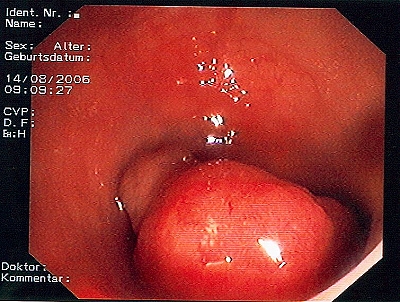

Großer Polyp des Dickdarmes